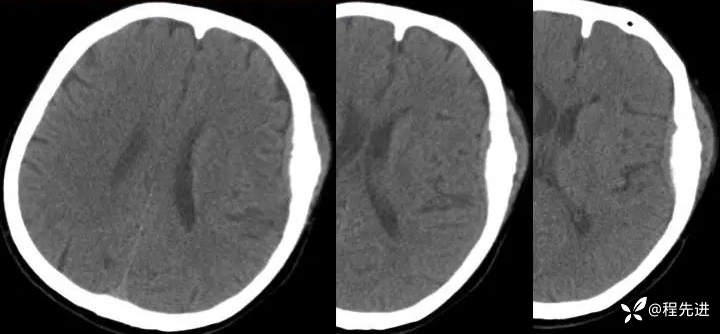

【患者信息】:女,58岁

【现病史及既往史】:发现头皮肿块,进行性增大2年余

影像检查:

2年后: